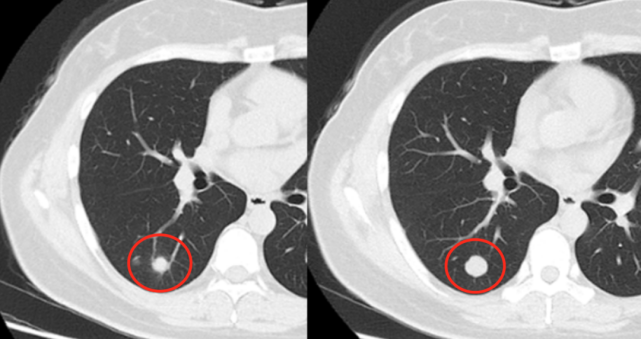

肺部结节ct图片图解

肺部结节ct图片图解,肺部小结节

肺部结节ct图片

肺结节ct图片 肺部

肺结节ct怎么看图解

怎样看懂肺结节ct图片